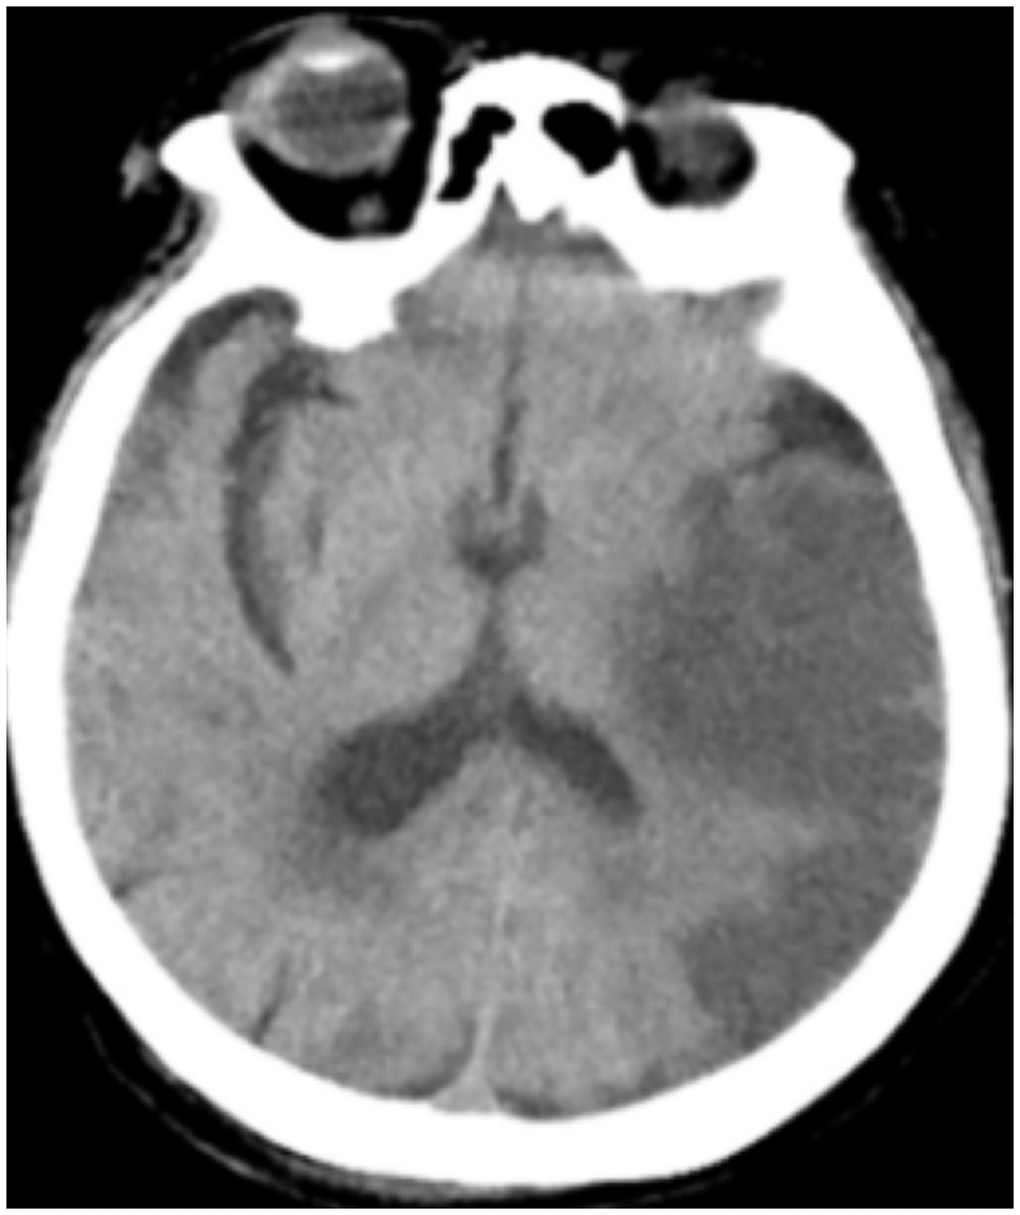

All patients were positive for the coronavirus nucleic acid test from pharyngeal swabs or blood. The blood lymphocyte counts and proportions of all patients were lower than normal (0.8×109/L) at the time of admission, and the white blood cell counts and proportions of six patients were higher than normal value (10×109/L). The blood D-dimer levels in all patients were higher than normal value (243 ng/mL) before neurological symptoms, and the C-reactive protein values in all patients were also higher than normal value (8000 μg/L). The chest CT of all patients showed flaky or frosted glass like- high-density shadow in lungs (Figures 1, 2), pleural effusion was seen in 2 cases (Figure 3), and no obvious abnormalities in 4 cases. The head CT imaging indicated that one patient had brainstem hemorrhage with ventricular cast and hydrocephalus (Figure 4), two patients had a large area of uniform low-density shadow on the frontotemporal lobe on the head CT (Figure 5), four patients had multiple flaky low-density shadow on the parietal lobe (Figure 6), one patient showed flaky low-density shadow in the pons (Figure 7), and three patients could see point-like low density shadow in basal ganglia (Figure 8).

Figure 5. Case 2, a large area of uniform low-density shadow on the left frontotemporal lobe.